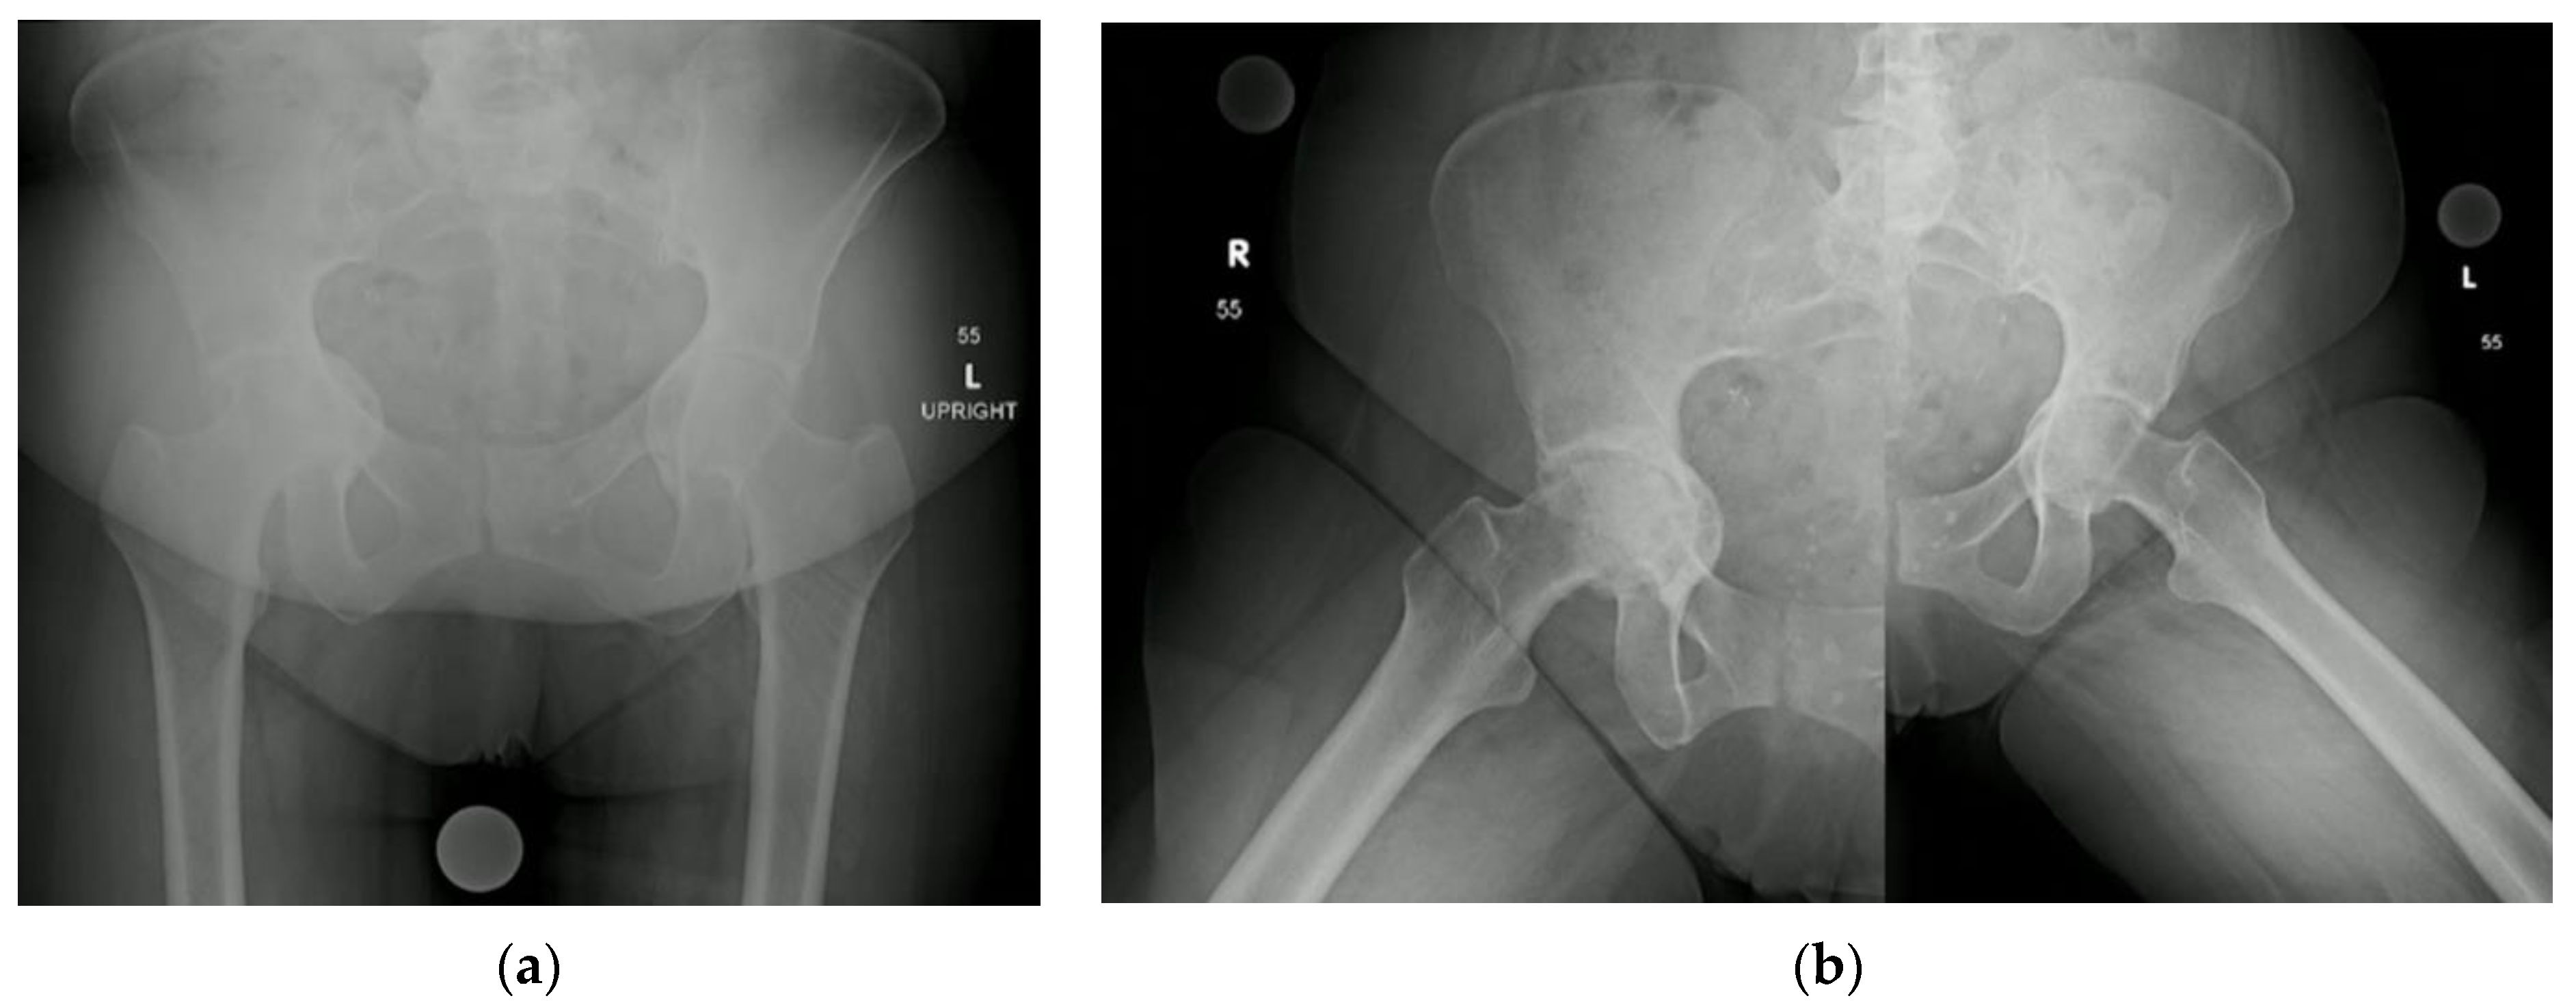

3.3. Protrusio Cases